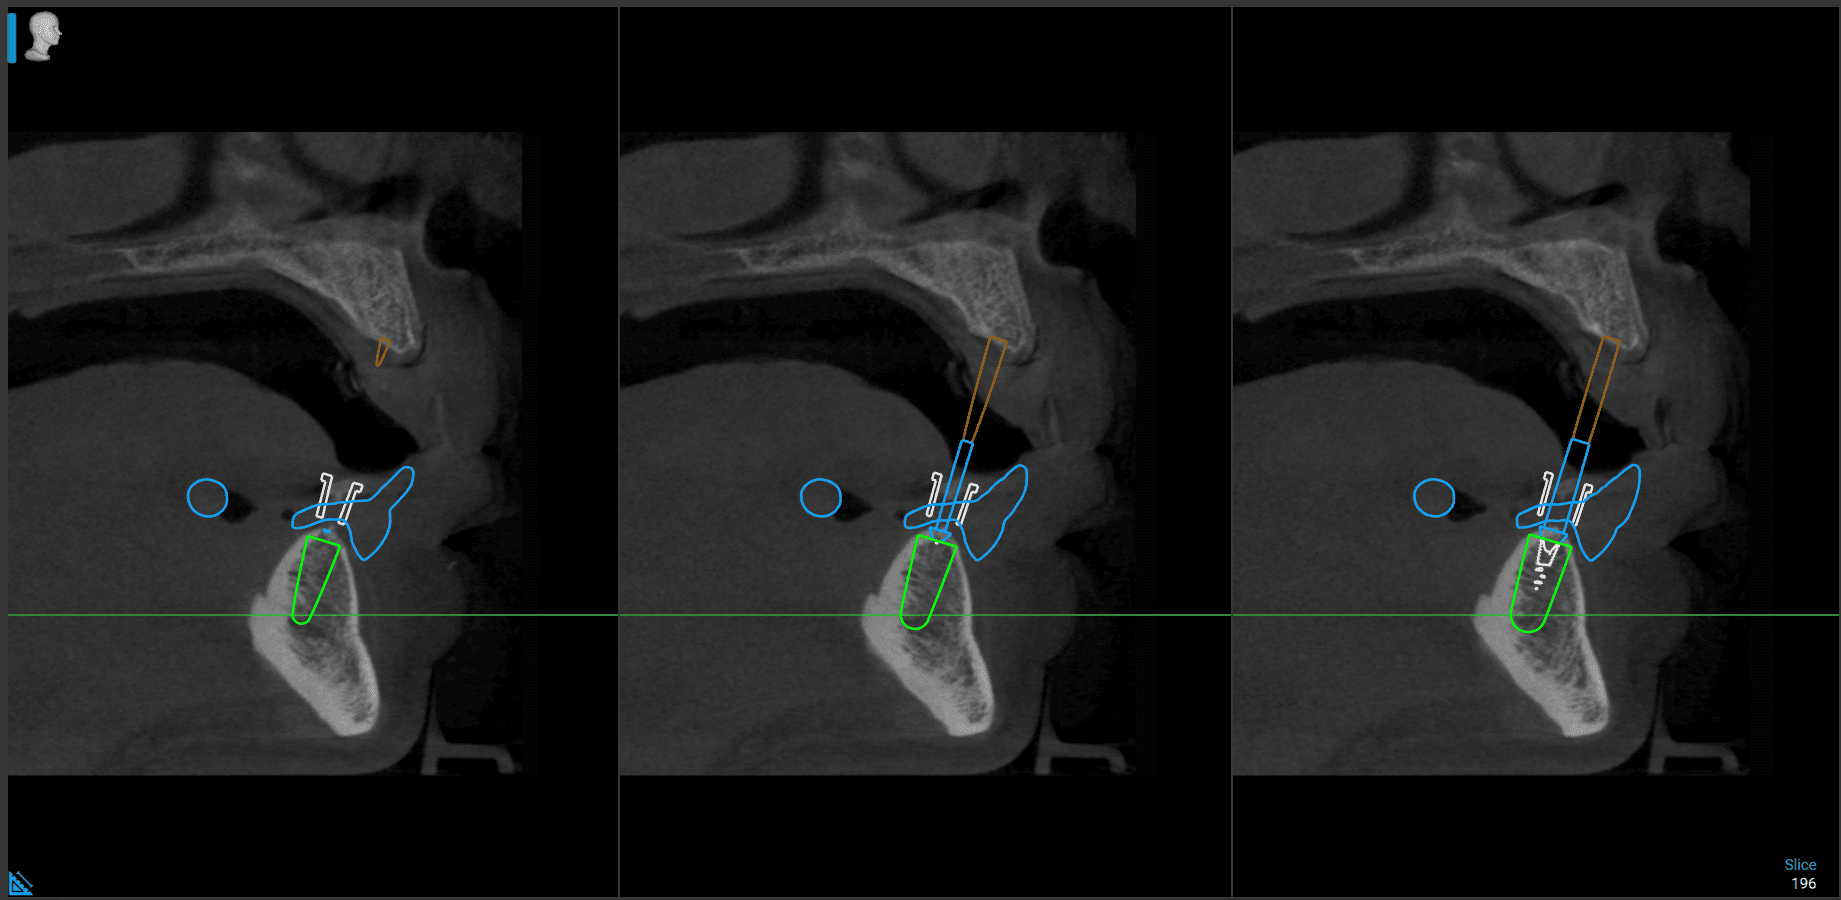

We merge CBCT scans, IOS files, and clinical records to create comprehensive, prosthetically guided plans. Every implant is positioned with anatomical awareness, surgical feasibility, and restorative intent from the outset.

Anatomical analysis and nerve mapping